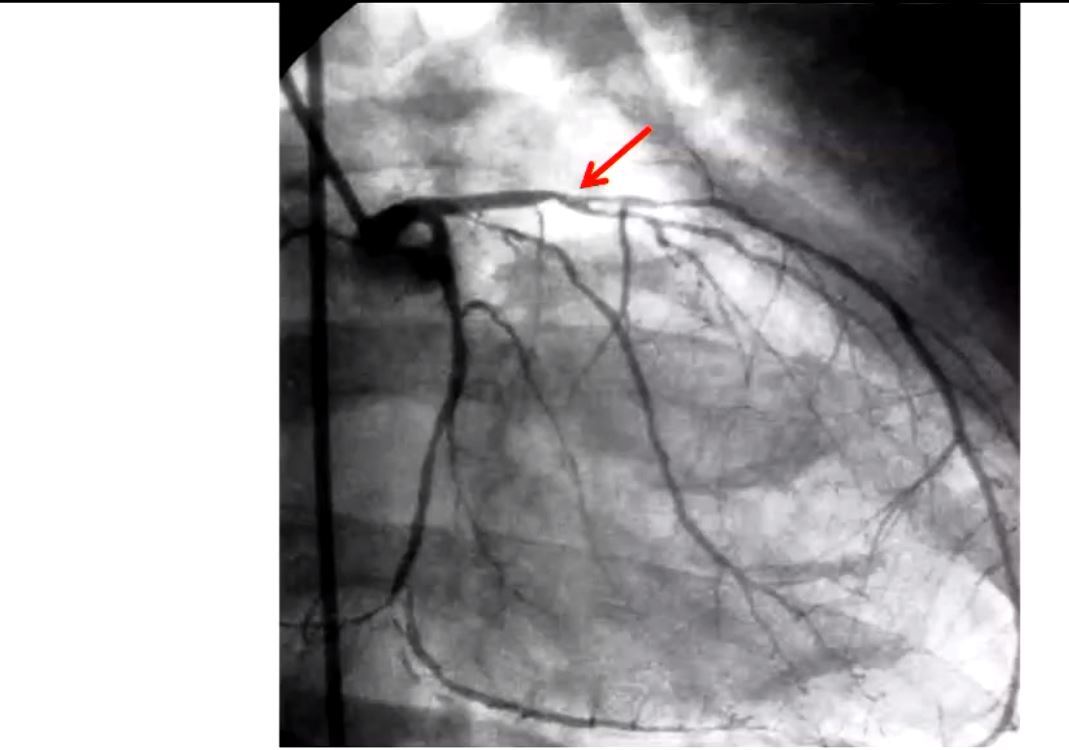

how to identify LAD on angiogram

goes towards apex

which CA is occluded

LAD